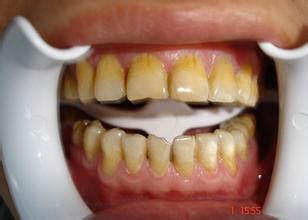

康贝佳医师指出,牙齿发育时,若服用了四环素类药物,药物进入体内后就在牙本质和牙釉质中形成黄色层,且牙本质中的沉积要比在釉质中高4倍。又由于黄色层呈波浪形,似帽状,大致与牙的外形一致,所以整个牙齿均有颜色的改变。>>>四环素牙的预防方法,在线咨询>>>

四环素牙更初牙齿呈黄色,在阳光照射下呈现明亮的黄色荧光,以后逐渐由黄色变成棕褐色或深灰色,这种颜色转变是缓慢进行的,阳光对它有促进作用。此外,四环素类药物不仅可以影响婴幼儿时期发育的恒牙牙色,而且孕妇若服用此类药物,还可以通过胎盘影响胎儿期发育的乳牙牙色。

四环素牙十分影响美观,如何治疗四环素牙呢?康贝佳口腔医师介绍说,一般来说中轻度的四环素牙可以选择进行冷光美白进行治疗,如果是中度的四环素牙可以选择进行牙齿贴面治疗,若四环素牙比较严重贴面已经难以遮盖,可以选择进行烤瓷牙冠修复美白。>>>四环素牙治疗多少钱?>>>